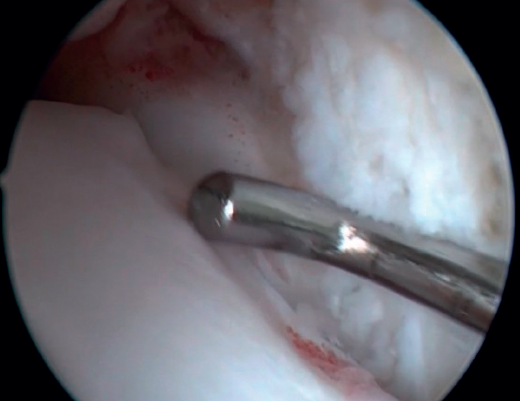

La resección de osteofitos se realiza deslizándose desde su parte superior, rebajando gradualmente hasta alcanzar la zona articular (Figura 2). Con una pinza de tipo basket se puede resecar la zona más cercana a la articulación (Figura 5). Suele ser útil intercambiar los portales de visión y trabajo para visualizar y resecar completamente los osteofitos. Para el pinzamiento de partes blandas, un sinoviotomo de 3,8 o 4 mm suele ser suficiente. El vaporizador es útil en pinzamientos compactos, típicos de condiciones postraumáticas o reintervenciones, también para delimitar la parte ósea del osteofito antes de su resección.

Figura 5. La resección de la parte más cercana al cartílago talar se puede completar con una pinza basket para minimizar el daño del cartílago articular.